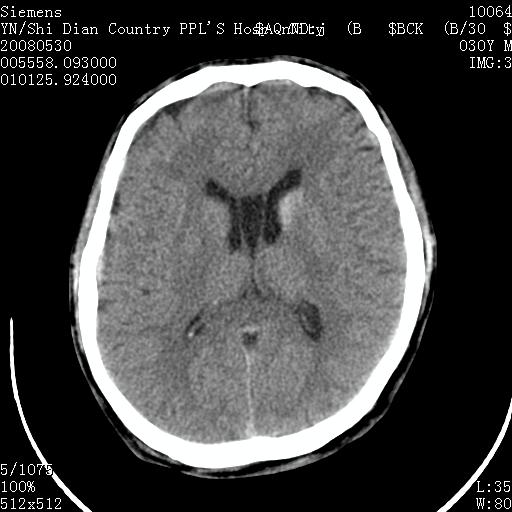

以下是引用pujunzhi在2008-7-10 13:06:00的发言:[br]透明间隔腔

以下是引用随光逐影在2008-7-10 15:19:00的发言:[br]1)考虑左侧尾状核钙化。2)透间隔间腔与vergae腔并存。

以下是引用卜一在2008-7-10 16:43:00的发言:[br]1)考虑左侧尾状核钙化。2)透间隔间腔形成。支持!